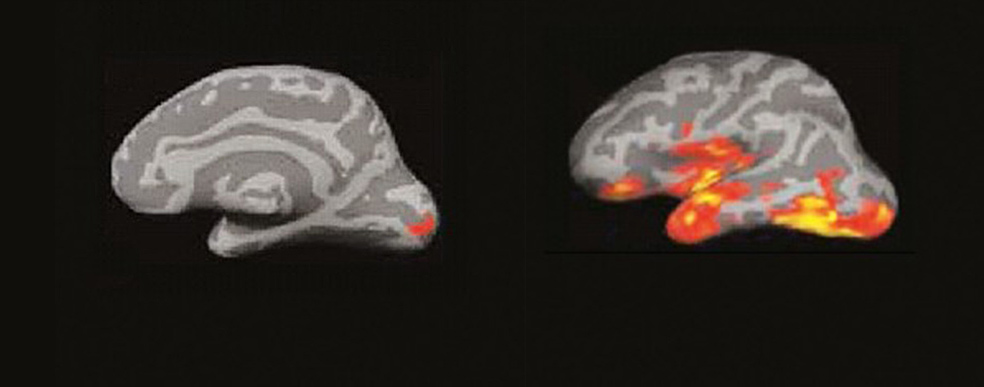

El cerebro del lector: un incendio de ideas

La imagen por resonancia magnética del cerebro de alguien que lee muestra algo parecido a un incendio forestal en un día de viento. Las pavesas vuelan y prenden nuevos conatos en diferentes zonas…